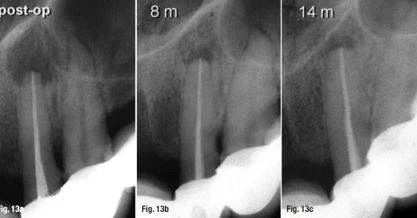

Kết hợp với bệnh  lý viêm kèm tiêu chân, việc xác định vị trị và quyết định điểm chóp cuối cùng trong nội nha đặc biệt khó khăn. Những quan điểm đang còn bàn cãi trong y văn cho rằng nên chọn điểm cách chóp 0.5 mm hoặc quá chóp 1.0 mm. Vì không có kỹ thuật chính xác nào cho những trường hợp như trên, vấn đề trở nên càng bế tắc cho các nhà lâm sàng (Hình 13a–c).

Bệnh lý kèm tiêu chân

Hình 13 a–c: Bệnh lý viêm kèm tiêu chân: Hình ảnh trước điều trị (a); sau 8 tháng (b); sau 14 tháng (c).